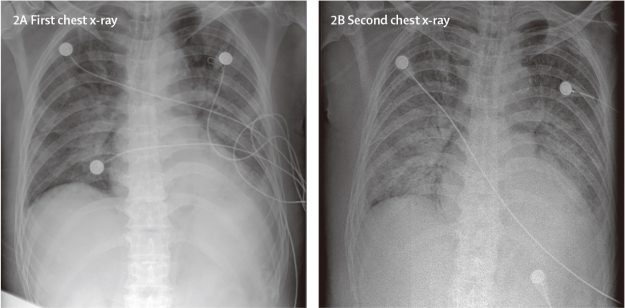

2020年1月10 日,我们登记一个6人的家庭,这个家庭成员曾在2019年12月29日至2020年1月4日从深圳去武汉旅游。6名家庭成员中有5名感染了新型病毒。此外,还有一个家庭成员没有去武汉,但在与4名家庭成员接触数天后感染了该病毒。这些家庭成员没有接触武汉的市场或动物,但其中两人去过武汉的医院。暴露3-6天以后,5名家庭成员(年龄在36-66岁之间)出现发热、上呼吸道或下呼吸道症状,并且伴随腹泻,或者上述综合症状。

新冠论文01 | 中国武汉2019新型冠状病毒感染病人临床特征

2019-nCoV,一种新的冠状病毒,引起了最近出现在中国武汉的多个肺炎病例。我们报道了这些肺炎病人的流行病学、临床、实验室、影像学等方面的特征以及采取治疗方法和临床结局。2019-ncov感染导致严重呼吸道疾病群集,类似于严重急性呼吸综合征冠状病毒引起的症状,并与ICU入院和高死亡率相关。目前对该疾病的起源、流行病学特征、人类传播持续时间以及临床疾病谱的认识存在不足,需要通过后续研究补充完善。